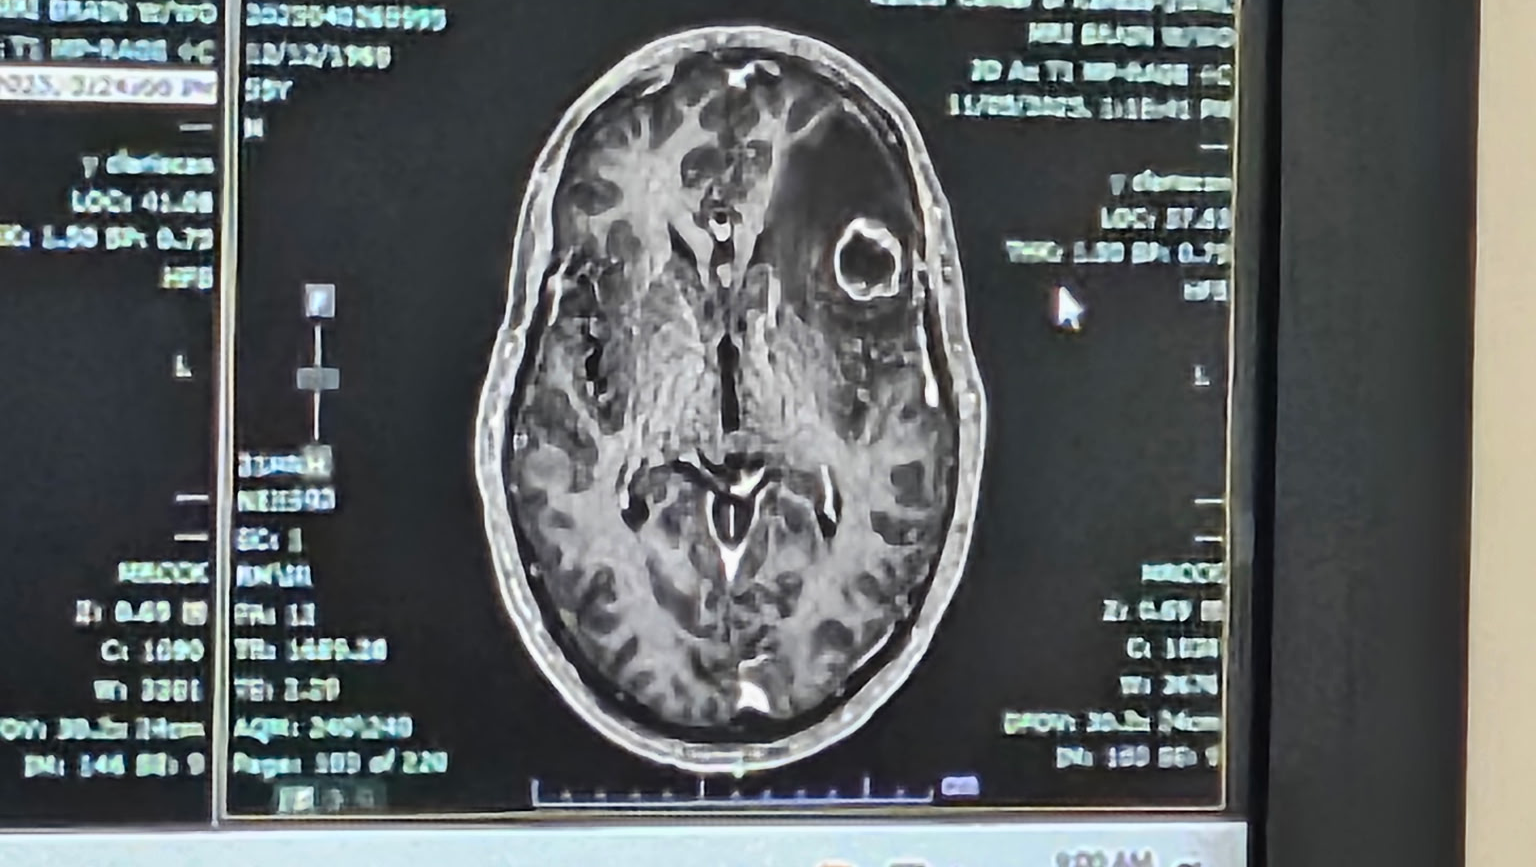

My father was diagnosed with cancer in March 2024. He has had a massive tumor on his left lung, pressing into nerves causing nerve damage and multiple brain tumors. We found out 4 weeks ago that he has a new tumor on his brain twice as big as his first one, causing swelling and memory loss.

My father was the sole provider for my mom and dad and now is unable to work. He was surviving on short-term disability through his employer, whom he worked for over 25 years. He now has no income and is in the process of trying to get disability through the state. He also is waiting on insurance approval to even start radiation on the new large tumor on his brain.